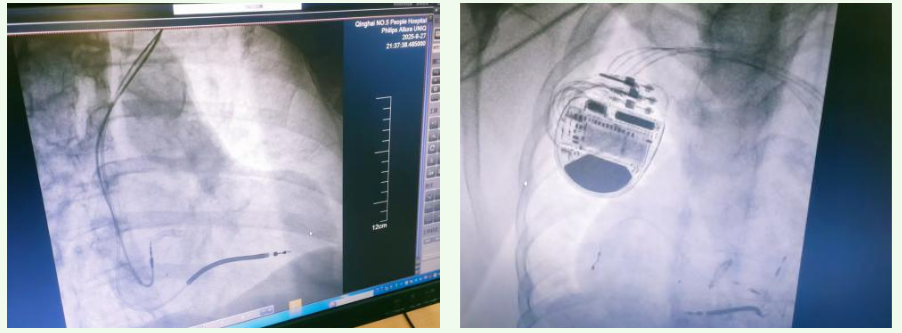

68岁的祁女士则有着长达10年的胸痛、胸闷病史,还曾在外院确诊为冠状动脉粥样硬化性心脏病、陈旧性心肌梗死等疾病,先后植入过七枚冠状动脉支架,近一年来接受内科纠正心衰优化药物治疗后,症状仍未得到明显改善。一周前,祁女士的胸痛、胸闷症状再次发作,来到青海省第五人民医院心血管内科就诊。经检查,除了原有基础疾病外,还被确诊为左心室附壁血栓形成、左心室心尖部室壁瘤形成等,心脏超声提示LVEF%仅为20.6%,存在极高的心脏性猝死风险。面对如此复杂的病情,医院心血管专家团队反复研讨诊疗方案,在充分排除手术禁忌后,为祁女士实施了“经皮植入式心脏复律除颤器(ICD)安置术”。术后,祁女士的心脏安全得到了有效保障,为后续康复奠定了坚实基础。 ▲手术过程及术后影像

同样被复杂心脏疾病折磨的还有52岁的郭先生,5年来,他因反复胸闷、气短、喘息多次就医,被诊断为“心肌病、心力衰竭”,药物保守治疗效果不佳。一个月前,郭先生受凉后症状急剧加重,不仅休息时也会出现胸闷、气短、喘息,步行轻微活动后还会晕厥,血压波动在极低水平。更棘手的是,郭先生有着40余年慢性乙型病毒性肝炎病史,还合并有肝炎后肝硬化、门静脉高压、腹腔积液等多种疾病,治疗难度大幅提升——由于血压显著偏低,纠正心衰的大部分优化药物都无法使用。 ▲手术过程 面对这一“难中之难”的病例,青海省第五人民医院心内科团队以患者生命安全为使命,组织多学科专家会诊,全面评估患者的身体状况,细致分析手术风险,最终确定方案,为患者实施“心脏再同步化治疗起搏器植入术(LOT-CRT-D)”。手术过程顺利,术后郭先生的血压明显上升至正常范围,此前频繁发作的晕厥症状消除,各项生命体征较术前得到显著改善,久违的笑容重新挂在了脸上。 ▲术前与术后心电图对比